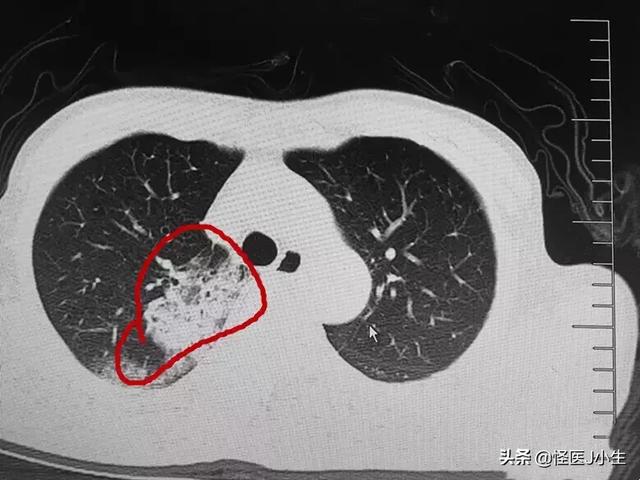

2. l'imagerie :Les radiographies du thorax et l'imagerie par tomodensitométrie des poumons peuvent révéler des zones d'ombre inégales dans les poumons, qui sont évidentes dans les bandes extérieures des poumons, et dans les cas les plus graves, des zones d'ombre solides dans les poumons peuvent être observées.

iii,Un scanner thoracique a été réalisé pour confirmer qu'une personne avait été exposée à une pneumonie à néocoronavirus sans symptômes significatifs de fièvre et de toux.Le diagnostic final de pneumonie à néocoronavirus peut être posé si le résultat suggère la présence de multiples ombres floconneuses en verre dépoli dans les deux poumons et si le test d'acide nucléique du nouveau coronavirus effectué sur un écouvillon de gorge se révèle positif.